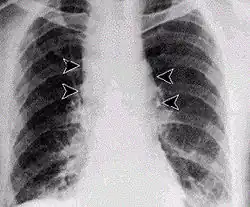

Lungenmilzbrand

Durch Einatmen von sporenhaltigem Staub entsteht der Lungenmilzbrand, auch Hadernkrankheit genannt.[10] Für einen Krankheitsausbruch (apparente Infektion) müssen ca. 3000–9000 Milzbrandsporen mit der Atemluft inhaliert werden, die an Tierhäuten oder Tierhaaren haften und noch nach Jahren ansteckend sind. Die Inkubationszeit beträgt einige Tage bis zu mehreren Wochen. Die Krankheit beginnt unspezifisch und grippeähnlich mit Husten, es folgen hohes Fieber, Schüttelfrost und Atemnot. Das ausgehustete Sekret ist hochinfektiös. Auch mit sofortiger antibiotischer Therapie (Ciprofloxacin, Doxycyclin, Penicillin G bzw. V) ist die Letalität (Sterbensrate) an Lungenmilzbrand sehr hoch, da mit dem Auftreten der Symptome eine massive Freisetzung der Milzbrandtoxine bereits stattgefunden hat. Der Tod tritt meistens innerhalb von drei bis sechs Tagen unter dem Bild eines septischen Schocks ein.